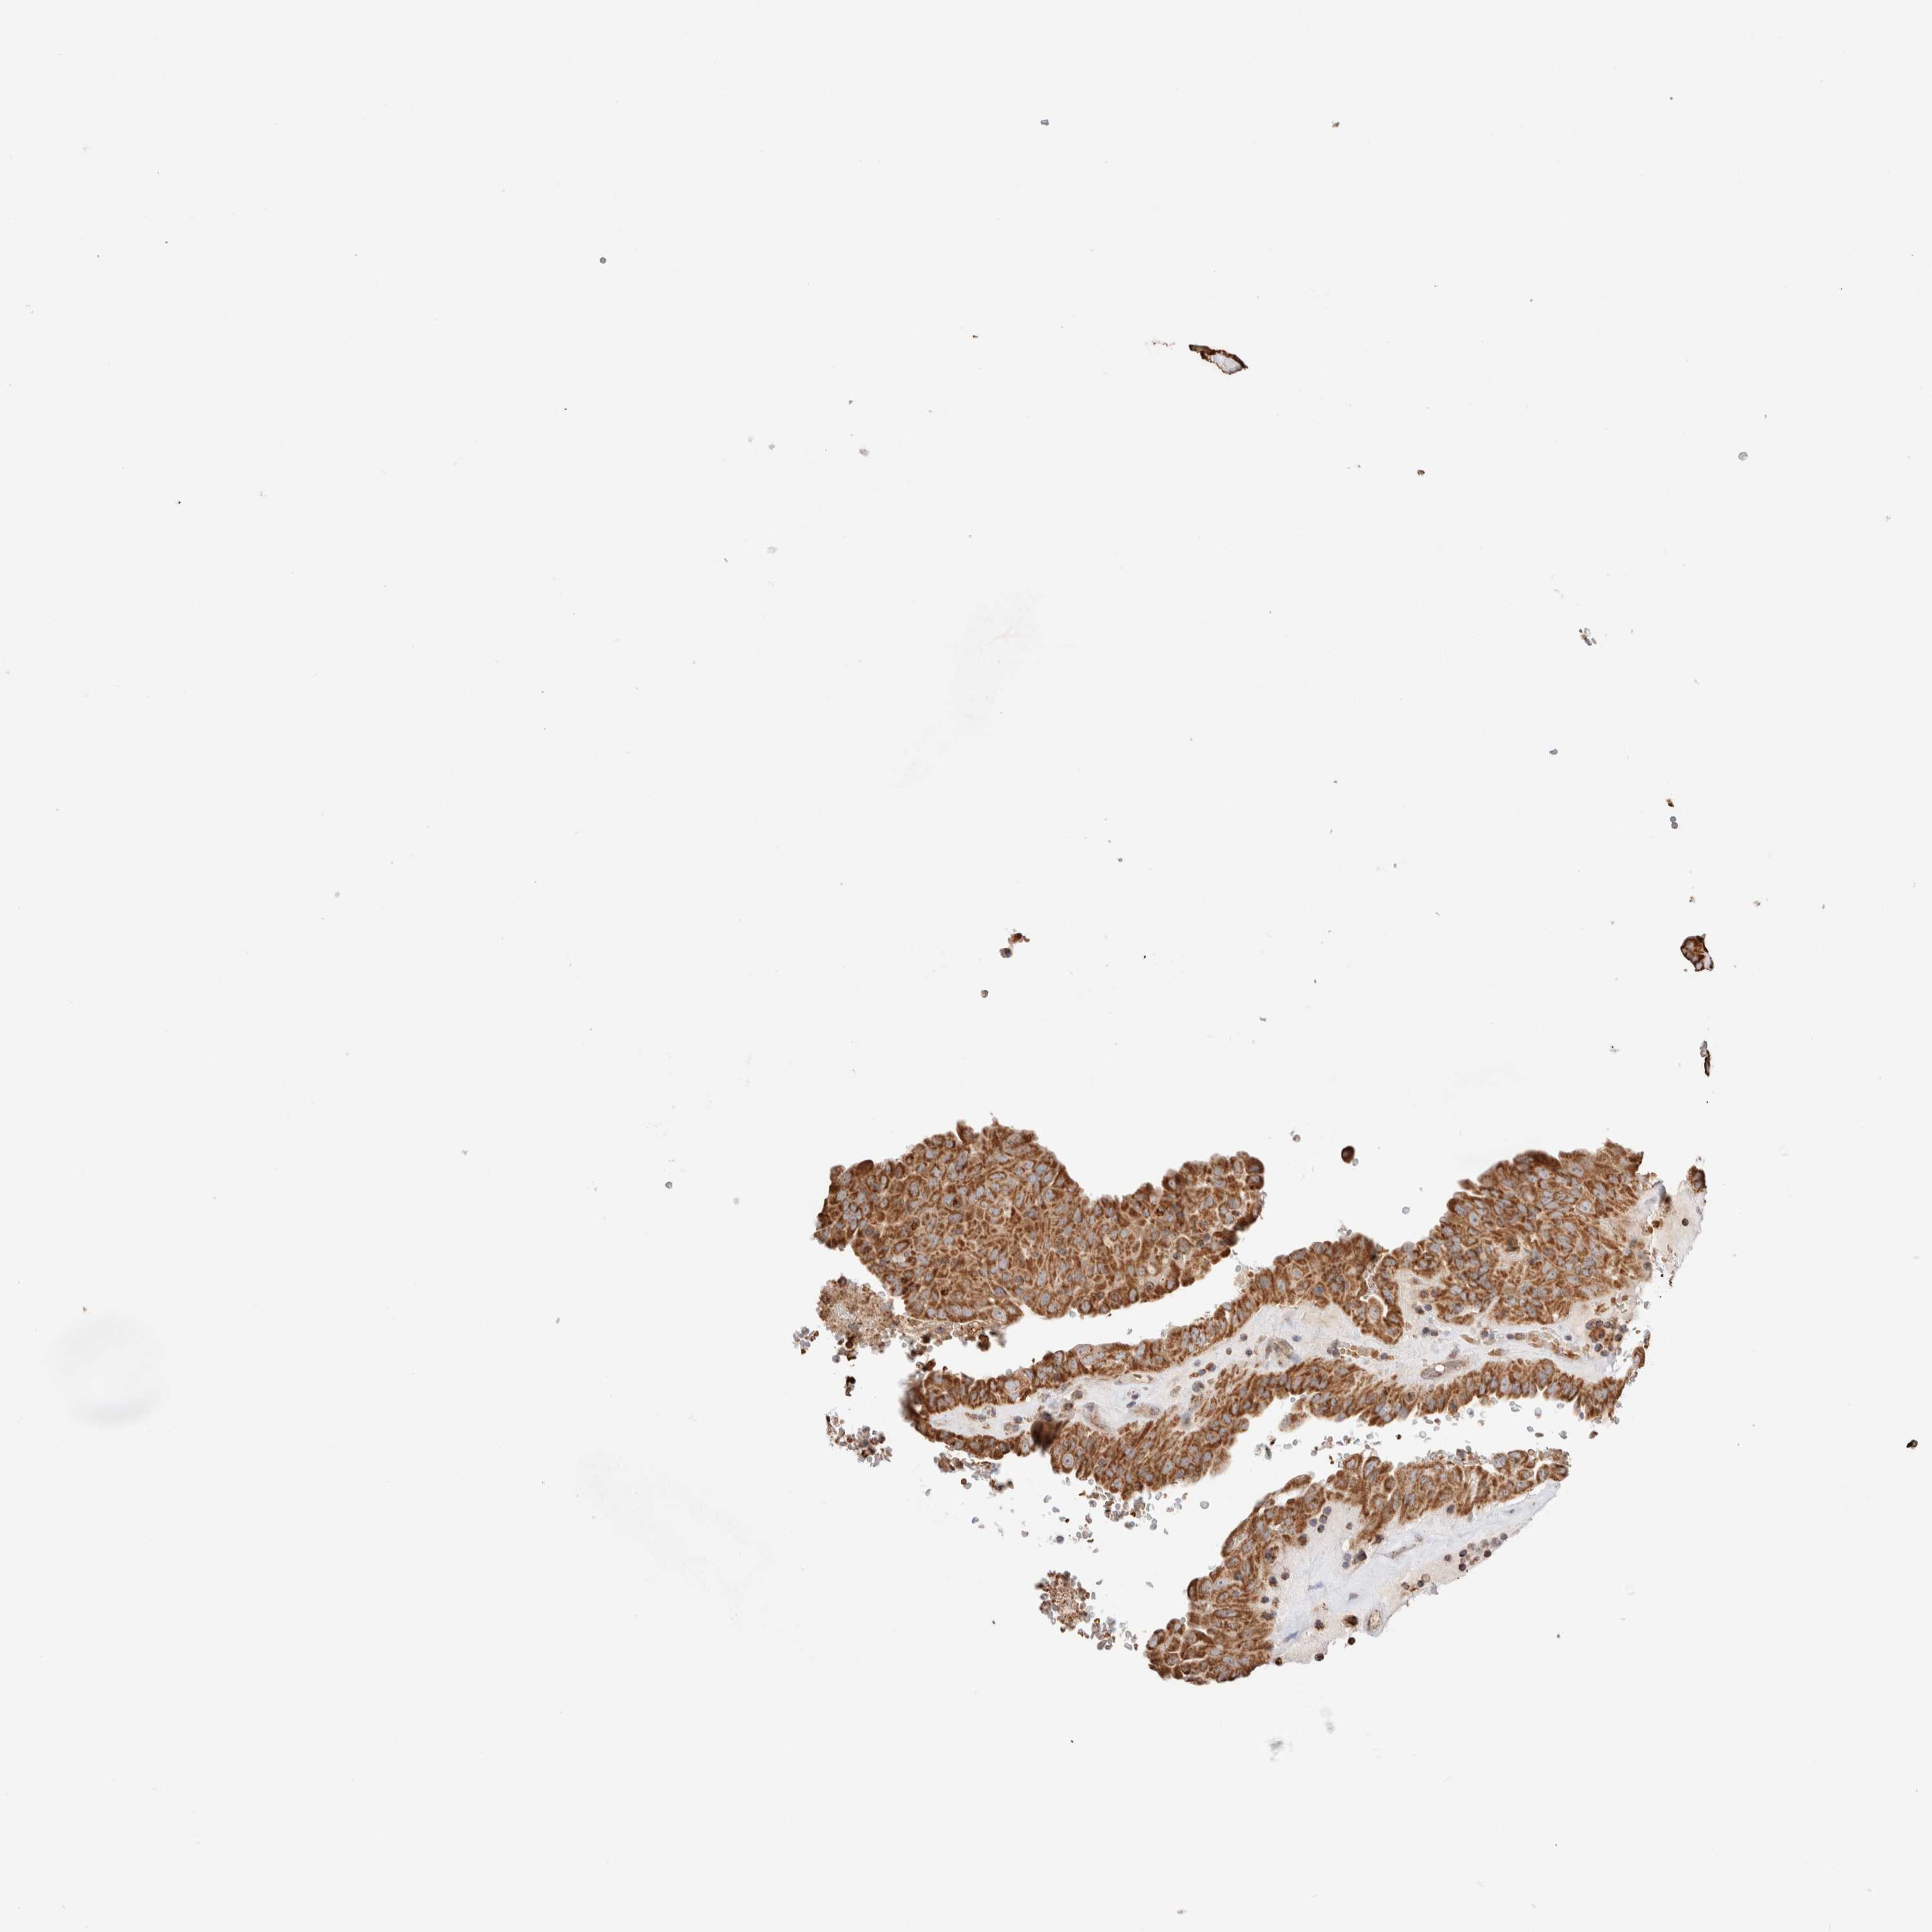

THYROID CANCER - Protein expressioni

A mouse-over function shows sample information and annotation data. Click on an image to view it in a full screen mode. Samples can be filtered based on level of antibody staining by selecting one or several of the following categories: high, medium, low and not detected. The assay and annotation is described here.

Note that samples used for immunohistochemistry by the Human Protein Atlas do not correspond to samples in the TCGA dataset.

Antibody stainingi

Antibody staining in the annotated cell types in the current human tissue is reported as not detected, low, medium, or high, based on conventional immunohistochemistry profiling in selected tissues. This score is based on the combination of the staining intensity and fraction of stained cells.

Each image is clickable and will lead to virtual microscopy that enables deeper exploration of all samples and also displays staining intensity scores, fraction scores and subcellular localization as well as patient and tissue information for each sample.

Antibody HPA027019

Staining

High

Medium

Low

Not detected

Intensity

Strong

Moderate

Weak

Negative

Quantity

>75%

75%-25%

<25%

None

Location

Nuclear

Cytoplasmic/membranous

Cytoplasmic/membranous,nuclear

Papillary adenocarcinoma, NOS

Follicular adenoma carcinoma, NOS